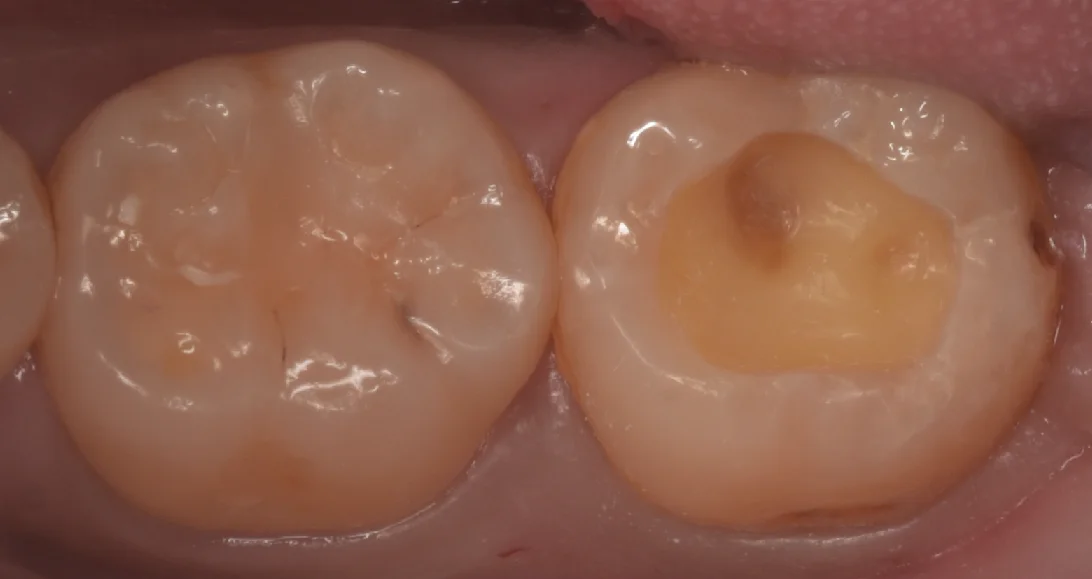

まずは術前からです。

この画面上の右側の白い詰め物の部分を再治療しました。

上から見た図なので少しわかりづらいのですが、非常に真っ平に、なおかつかなり窪んだ状態で詰められていたため、食べ物がそこに溜まりやすい状態になっていました。

またこれほど真っ平らな場合は食べ物の排出の際に応力がかかってしまうため詰め物が結果として持たなくなってしまいます。

歯の溝は無駄についているのではなく必要だからついているわけですからね。